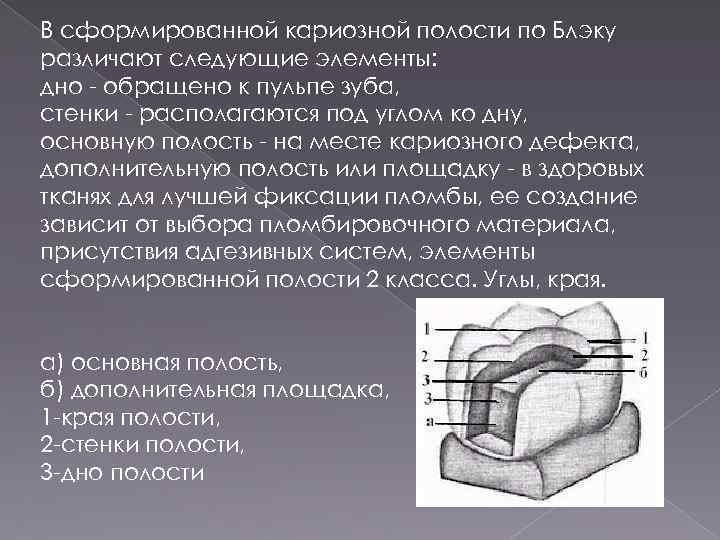

Раздел: Необычные решения